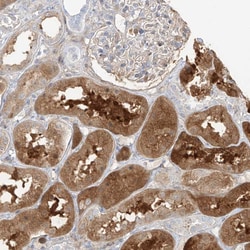

| Immunohistochemistry (Paraffin), Western Blot, Immunocytochemistry | |